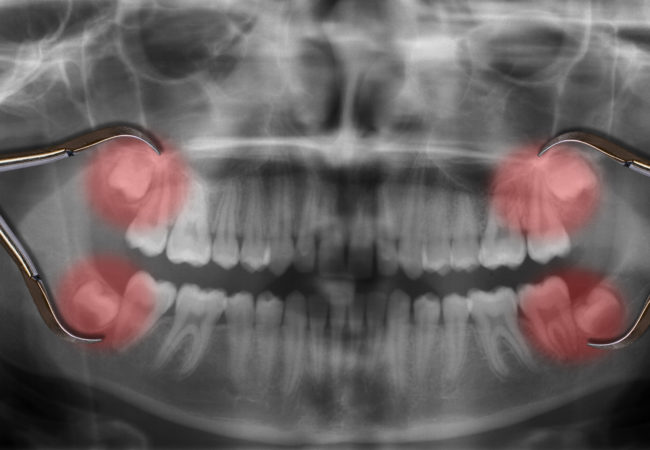

With an oral examination and x-rays of the mouth, Dr. Rachana Vora can evaluate the position of the wisdom teeth and predict if there are present or future potential problems. Studies have shown that early evaluation and treatment result in a superior outcome for the patient. Patients are generally first evaluated in the mid-teenage years by their dentist, orthodontist, or by an oral and maxillofacial surgeon.

If you do not have enough room in your mouth for your third molars to fully erupt, a number of problems can happen. Impacted wisdom teeth should be removed before their root structure is fully developed. In some patients it is as early as 12 or 13, and in others it may not be until the early twenties. Problems tend to occur with increasing frequency after the age of 30. Some of the possible problems related to not removing your wisdom teeth include: